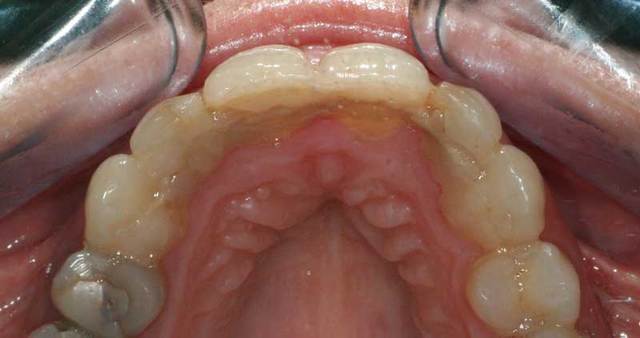

ça c'est de la contention.

je vais démonter cette contention et essayer de faire un peu mieux que ça.

quelle est la meilleure méthode pour faire une contention au maxillaire, sachant que les latérales vont sûrement avoir des facettes ou des couronnes.